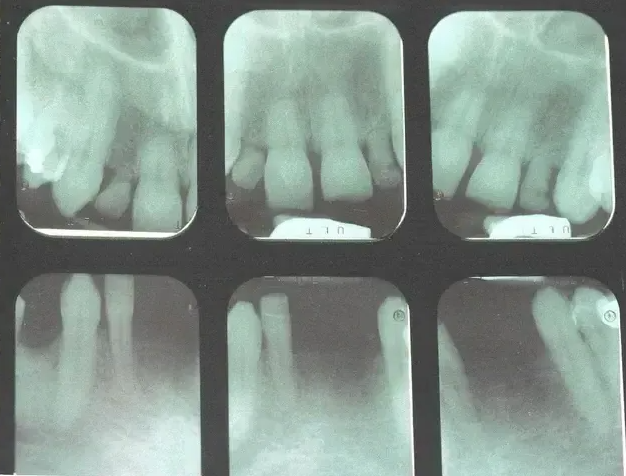

Options treating adult patient with multiple congenitally missing permanent front teeth.

Treating adult patients with multiple congenitally missing front teeth can pose many issues. If they are misaligned, broken, or have been missing for decades dental implants may not be possible. Due to inadequate bone often such patients need different restorative solutions.

Here is a patient we recently treated at our office who had six congenitally missing front teeth. After removing retained baby teeth three ceramic bridges were placed restoring this patients smile and bite. These bridges were made of zirconia and porcelain and look like natural teeth. No metal was present in these bridges so no black or grayish appearance at the gumline like older crowns and bridges. This patient ad his wife both felt this treatment changed his life. He can now smile without being self-conscious the first time in decades.